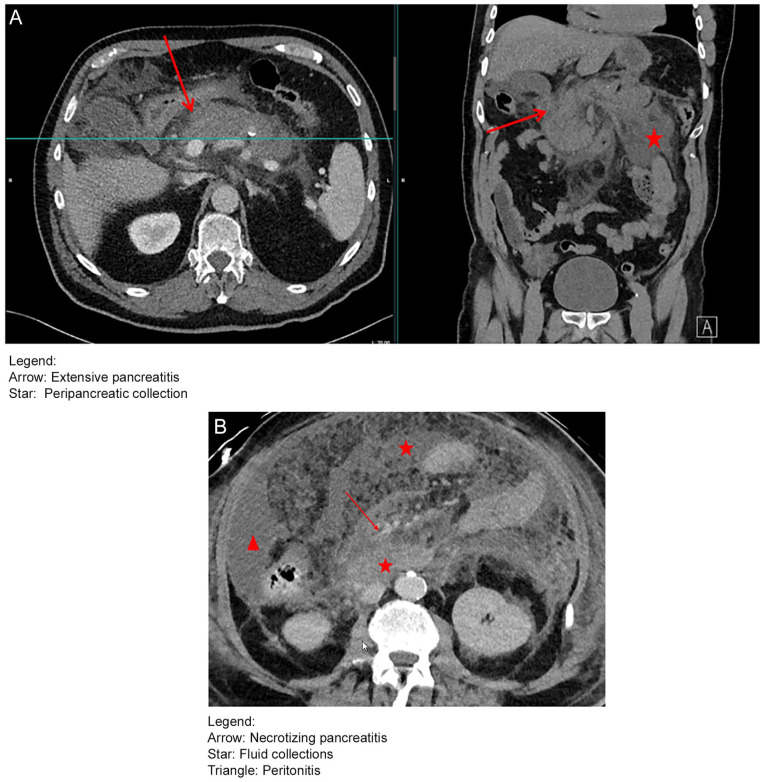

Several adverse effects have been reported following the use of the Pfizer-BioNTech mRNA vaccine against COVID-19 infection with acute pancreatitis being one of those. However, a direct relationship between the vaccine and the occurrence of acute pancreatitis has not been confirmed. Hereby, a case of an acute necrotizing pancreatitis resulting in fatal outcome following the administration of the COVID-19 BioNTech Pfizer vaccine is presented. A 70-year-old male presented with abdominal pain 4 days after receiving his fifth dose of the COVID-19 BioNTech Pfizer vaccine. Laboratory examination showed lipase levels of 2000 U/L. A CT scan was performed and showed necrotizing pancreatitis. After detailed evaluation, no etiological cause of pancreatitis could be found in this patient. The patient was admitted to the intensive care unit. After a disease course of ~6 weeks, the patient died due to multiorgan failure. This case presentation takes into account previously reported cases of acute pancreatitis following COVID-19 vaccination. To our knowledge, this is the first case of acute pancreatitis with fatal ending following a COVID-19 vaccination. This highlights the importance of thorough evaluation of patients presenting with abdominal pain following the administration of a COVID-19 vaccine.